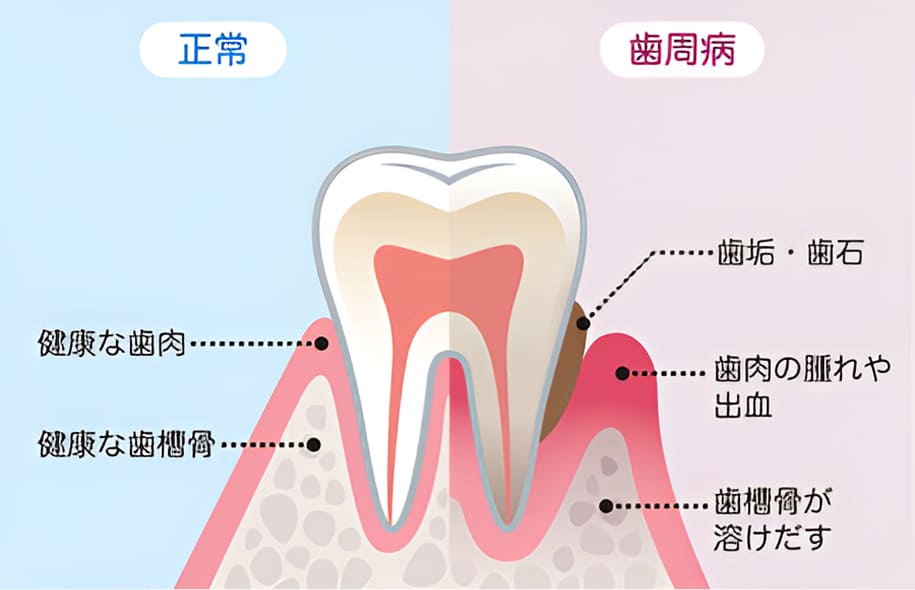

自覚症状が少ない歯周病は

早期発見・治療が重要です

歯周病は細菌感染によって歯の周りの組織が破壊され、最悪の場合は歯が抜け落ちてしまう疾患です。初期段階では自覚症状が出にくい特徴があるため、異変を感じたらすぐに治療を受けることが大切です。当院では、治療前に検査を実施して歯周病の原因・進行度を診断し、治療計画を立てて治療を進めていきます。

歯周病が及ぼす全身への影響

歯周病はお口の中だけの病気だと思っていませんか?歯周病はお口の中だけでなく、全身に影響を及ぼす恐ろしい病気です。

歯周病菌によって深い歯周ポケットが作られると、そこから細菌や病原菌が歯肉の血管を通じて血液に流れ込みます。

これによって全身に運ばれ、組織や臓器に影響を及ぼしてしまうと考えられています。

近年ではさまざまなリスクが明らかになっており、以下のような全身疾患との関わりが分かっています。

日本人の成人の多くの人がかかっていると言われる歯周病は、治療が遅れるほど負担が大きくなります。

歯周病治療は、はじめに口腔内の状態を診査し、その結果をもとに治療方針を説明。患者さんの理解、同意を頂いてから治療を開始します。

治療では必要に応じ排膿や噛み合わせの調整などの応急処置を施し、その後はプラークコントロールやスケーリングなどを行い歯茎の健康を取り戻していきます。